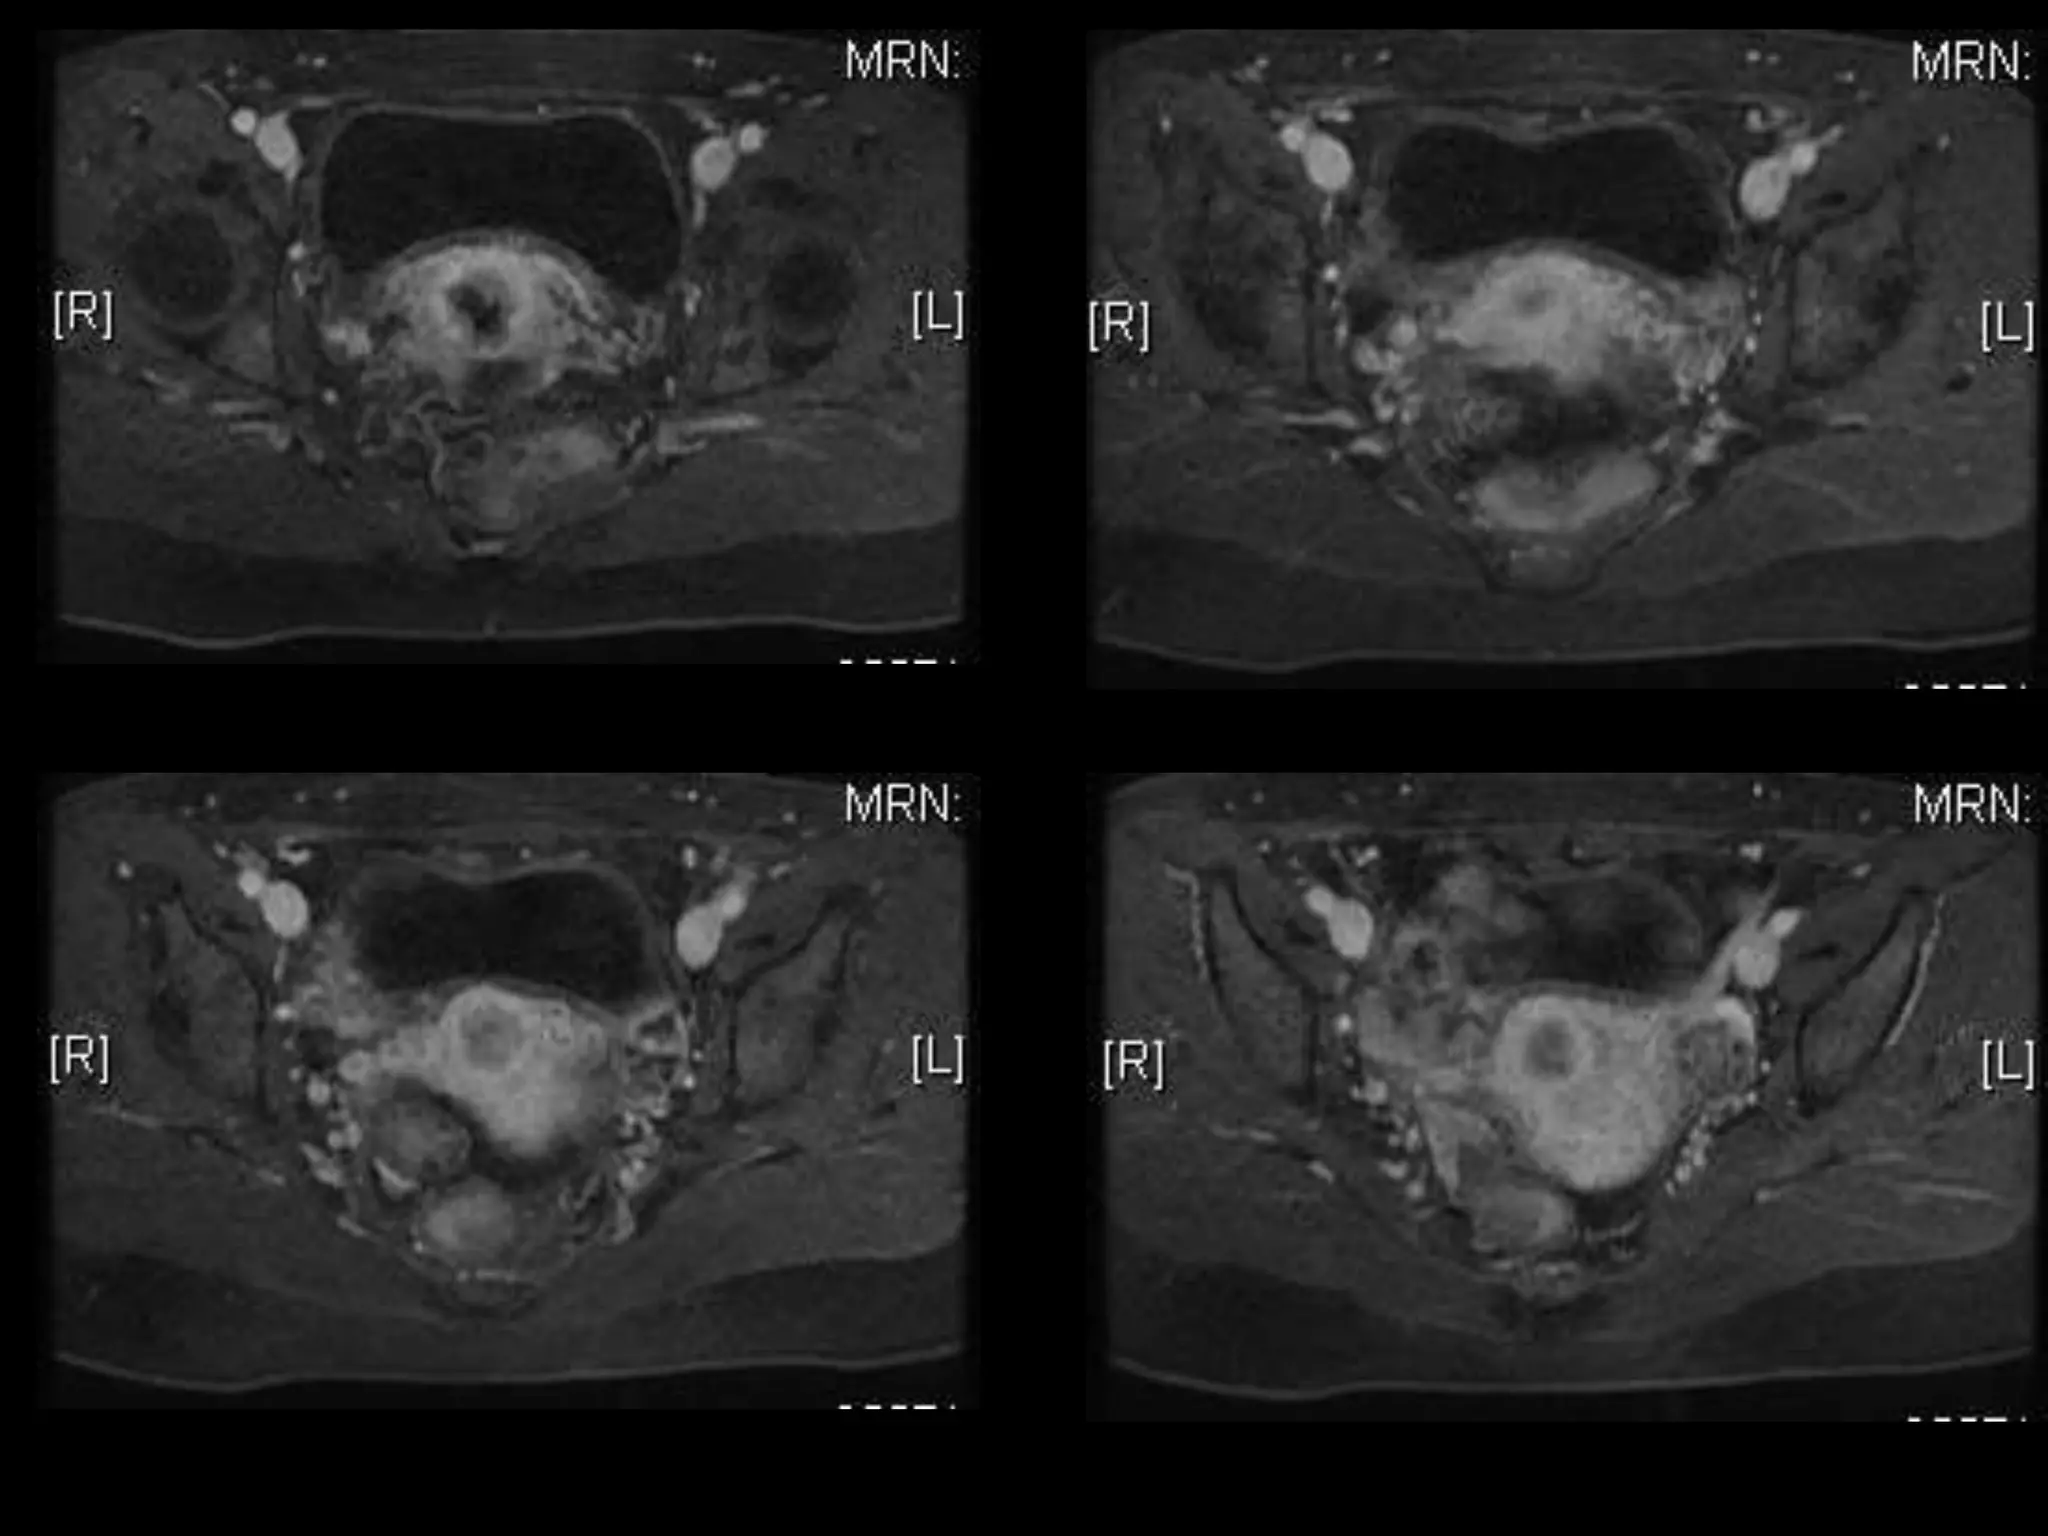

MRI findings - Stage IIB

with PET/CT - Stage IIIB

HISTORY โ€ข 42 yo female โ€ข Recent immigrant from China โ€ข C/O postcoital and intermenstrual bleeding โ€ข Abnormal GYN exam โ€ข Abnormal biopsy โ€ข Further imaging performed

MRI findings -Stage IIB with PET/CT - Stage IIIB Cervical Cancer

Stage I โ€“Carcinoma Confined to Cervix <= 4 cm greatest dimension > 4 cm greatest dimension <= 7 mm wide A1 < =3mm deep A2 >3 but < 5mm deep

Stage II โ€“Carcinoma Invades Beyond Uterus But not to Pelvic Wall or Lower 1/3 Vagina With(A) or without (B) parametrial invasion

Stage III โ€“Carcinoma to Pelvic Wall and/or Lower 1/3 of Vagina and/or Causes Hydronephrosis or Nonfxing Kidneys Lower 1/3 Vagina No pelvic wall Extends to pelvic wall and/or renal issues

Stage IV โ€“Carcinoma beyond True Pelvis or Involvement Of Mucosa of Bladder or Rectum (bx proven) Distant Mets Spread to adj organs

Role of MRImaging in Tx Stratification of GYN (Cervical) Cancer โ€ข Cervical Cancer โ€“ 2nd most common ca in women worldwide โ€“ Developing countries; pk 30-40 yrs โ€ข FIGO classification โ€“ revised in 2009 from just clinical to incorporate cross-sectional imaging (CT, MR) โ€ข Staging accuracy of MR 85-96% โ€“ Best test to assess tumor size and location; invasion into parametria, pelvic side wall, adjacent organs; local nodal enlgment โ€ข PET/CT helpful in staging advanced disease โ€“ Demonstrates unexpected sites beyond pelvis โ€ข Treatment options โ€“ Radical surgery - early stage (IA, IB1, IIA1) โ€“ Primary Chemo and Radiation โ€“ bulky IB2 or IIA2, or local advanced (IIB or greater) Sala et al. Radiology 2013; 266: 717.